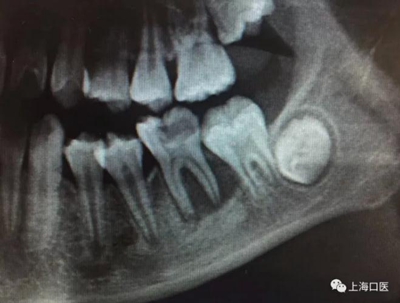

這是上海武廣增正畸工作室接診的一例非常規(guī)拔牙矯治病例,患者女性,初診年齡14歲。LL6殘冠拔除。LL7近中平移取代LL6,我們上傳了該患者一組下頜磨牙近中平移連續(xù)矯治過程的正畸X線片,與正畸界朋友分享。

來源:武廣增 上??卺t(yī)